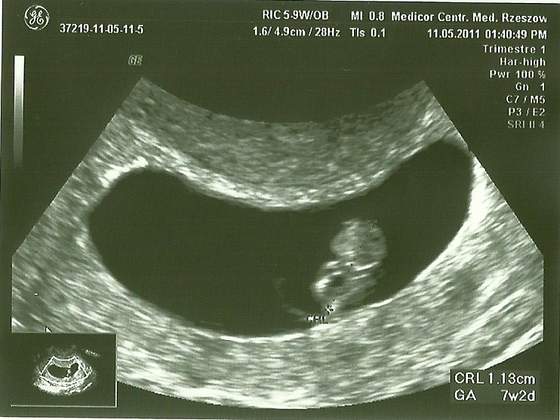

możesz spodziewać się o takiego widoczku:

Zobacz załącznik 386171 to było moje pierwsze zdjęcie maluszka, jak się okazało na połówkowym - córeczkipierwsza wizyta - 8 tydz